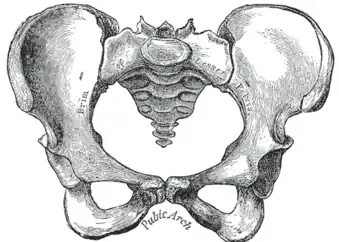

-

Becken -

Geschlechtsunterschiede am knöchernen Becken und Variationen

Das weibliche und männliche Becken beim Menschen unterscheiden sich deutlich. Während bei der Frau die beiden Beckenschaufeln ausladender sind und das Hüftbeinloch (Foramen obturatum) eine eher dreieckige Form hat, ist das männliche Becken hoch, schmal und eng. Auch der Beckenausgang ist beim weiblichen Becken breiter; der Winkel zwischen beiden Schambeinästen ist beim weiblichen Becken größer als 90° (Arcus pubicus), während er beim männlichen Becken nur etwa 70° (Angulus subpubicus) beträgt. In der Anatomie und der Geburtshilfe werden zur Beschreibung der Beckenform standardisierte Conjugata (Ansicht von lateral) und Diameter (Ansicht von kranial oder kaudal) verwendet.